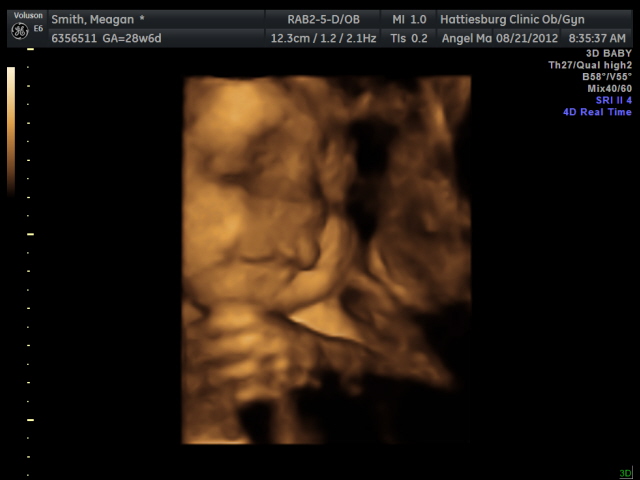

Also, I will leave you with this. I hope you think it’s cute instead of creepy. I think he looks like he is smiling…